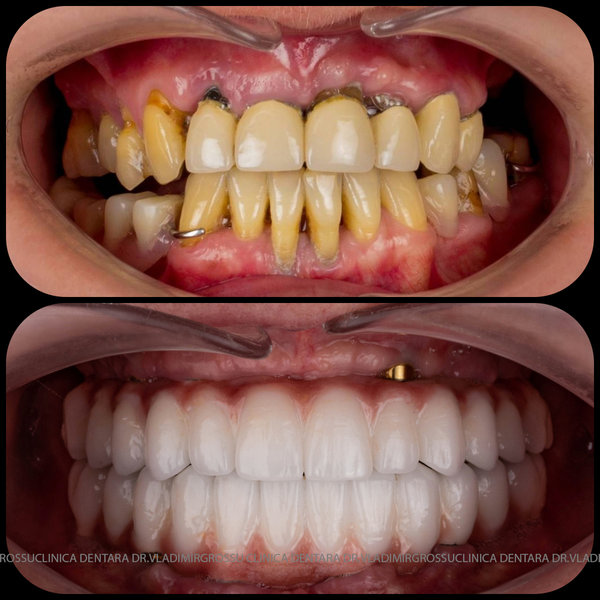

Cazuri clinice conceptul All-on-6

Caz 2